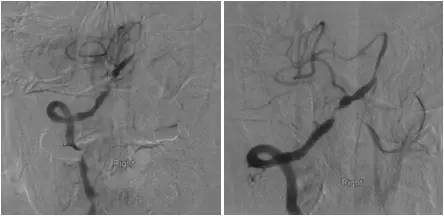

患者一个月前劳累后出现头晕,间断发作,每次持续约5-6分钟,可自行缓解。初未引起重视。其后因症状反复且程度加重,当地医院就诊,行MR提示桥脑及左侧小脑有新发梗死灶(图1)。

图1

MRA:基底动脉中远段重度狭窄,右后交通动脉开放,左胚胎型大脑后动脉,双颈内动脉颅内段及双大脑中动脉多发轻-中度狭窄(图2)。

图2